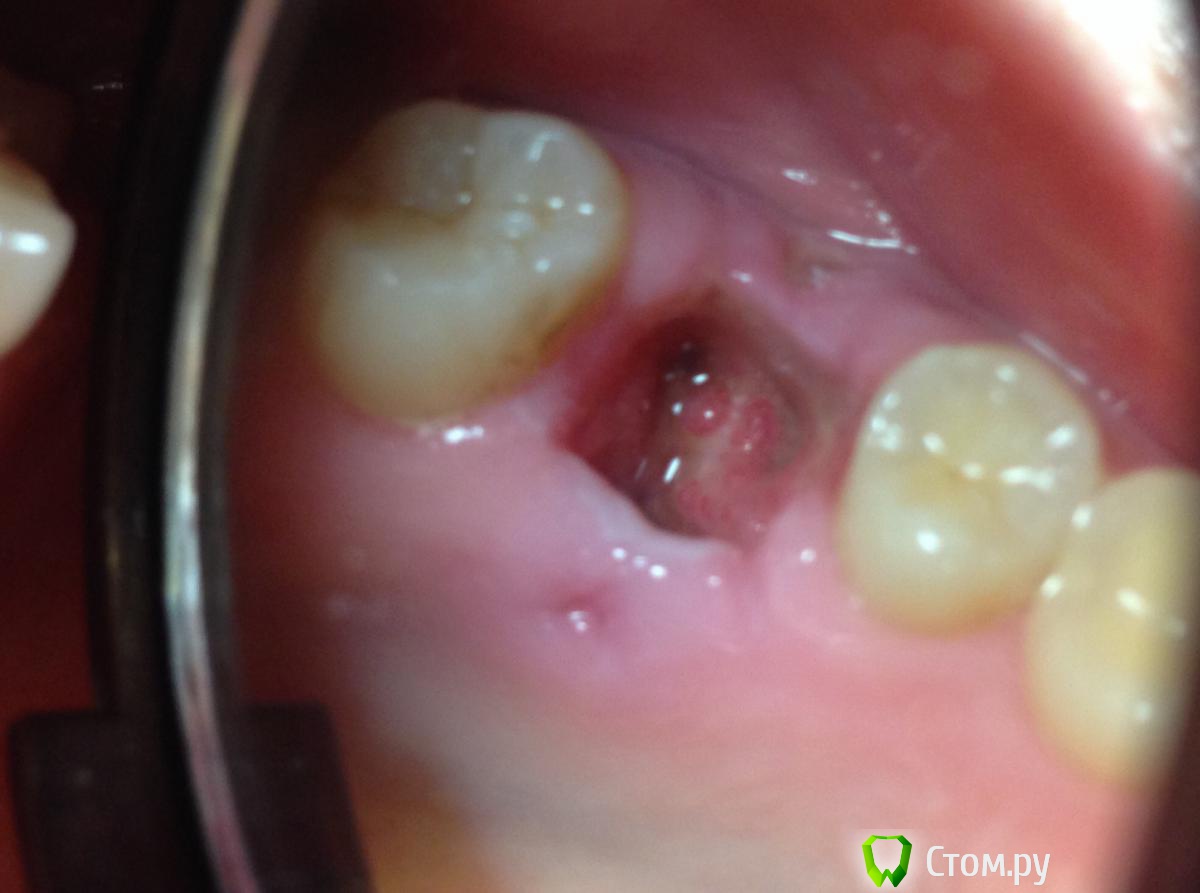

5 июня пошла к тому врачу, который удалял зуб. Сделал снимок - в десне небольшие остатки старого лечения каналов, сказал это нормально. Лунку прочистил, сказал сгустка нет, это просто забилась еда. При вычищении было жутко больно, снова пошла кровь. Никаких лекарств он при этом не применял. Назначил аккуратные полоскания с Тандум Верде и мазь Солкосерил.

С Солкосерилом стало намного легче, ибо дырка стала просто огроменной. Замазываю ее периодически, чаще перед едой. Температура 37

С момента удаления зуба прошло 9 дней. Солкосерил уже бесит, но без него еще хуже. Еще и дырка небольшая появилась в десне после зашивания, на фото видно. Все слишком плохо? Что делать дальше? Нужны ли физио процедуры, антибиотики, что-то еще?

post-39094-0-70653400-1402226507_thumb.jpg

По Вашим фото снимкам (предварительно)  кроме  " банального"  альвеолита ничего на ум не приходит)